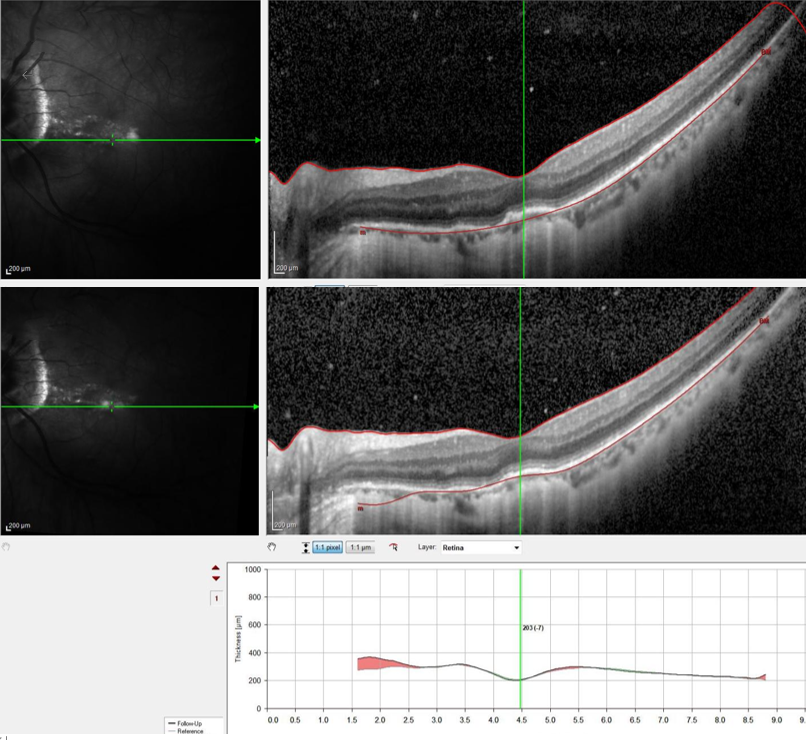

为明确病因,诊疗团队为李叔叔安排了扫描激光眼底检查 (SLO)、光学相干断层成相 (OCT) 及眼底造影检查。结合检查结果与临床表现,最终精准确诊李叔叔患的是多灶性脉络膜炎合并多发性一过性白点综合征——这是两种较为少见的眼底疾病,叠加发病后病情更为复杂,若延误治疗,可能导致视力永久性丧失。

针对李叔叔的复杂病情,科室制定了个性化的治疗方案,予以全身及局部激素球旁注射规范治疗。治疗期间,医护团队密切关注李叔叔的病情变化,及时调整治疗细节。经过一段时间的精心治疗,李叔叔的病情逐渐好转,左眼视野慢慢恢复正常。虽然因病灶累及黄斑中心凹,视物仍遗留中心暗点,但最佳矫正视力已恢复至 0.1,相比就诊时的状态有了质的飞跃。「能恢复到这个程度,我已经非常满意了,特别感谢辽宁爱尔的医护人员!」复查时,李叔叔激动地说道。